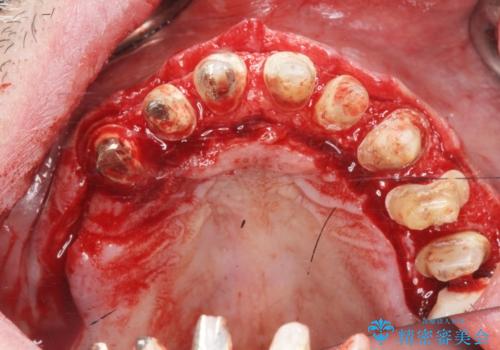

- 「セラミック治療を他院で受けたが、それ以来歯ぐきが腫れ違和感がある、改善してほしい。」と歯ぐきの状態改善を希望され来院されました。

歯周組織検査を行うと歯ぐきからは容易に出血し、X線検査より歯とセラミッククラウンの適合が悪い(ピッタリと合っていない)状態が示唆され、歯ぐきの炎症を惹起している状態でした。

セラミッククラウンを除去し仮歯を装着し、歯周外科手術を行い歯ぐきの状態を改善したのち、適合の良いセラミッククラウンを再作製をする治療計画としました。